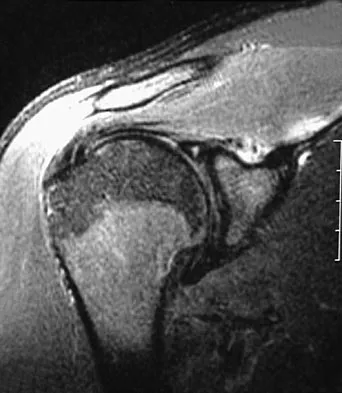

A 72-year-old woman who fell on her right shoulder while using a treadmill is now unable to elevate her right arm. An MRI scan is shown in Figure 7. What is the most likely diagnosis?

The MRI scan reveals a large chronic rotator cuff tear with retraction and fatty infiltration atrophy of the supraspinatus and infraspinatus tendons. This tear is responsible for the patient's severe weakness and inability to elevate the arm.